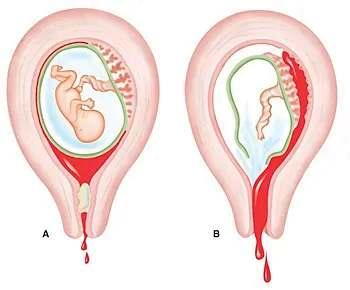

ABORTO

El aborto consiste en la interrupción del embarazo y se puede producir tanto inducir. Sea cuál sea el caso el aborto incluye con la expulsión del feto a través del anal vaginal.

ï Aborto espontáneo: Es aquel que no se da de forma intencionada sino a causa de una serie de complicaciones en el feto o a la madre. Generalmente ocurre durante las 12 primeras semanas de gestación y no precisa de ningún tipo de intervención quirúrgica pero a partir de la semana 20 pasa a denominarse muerte fetal